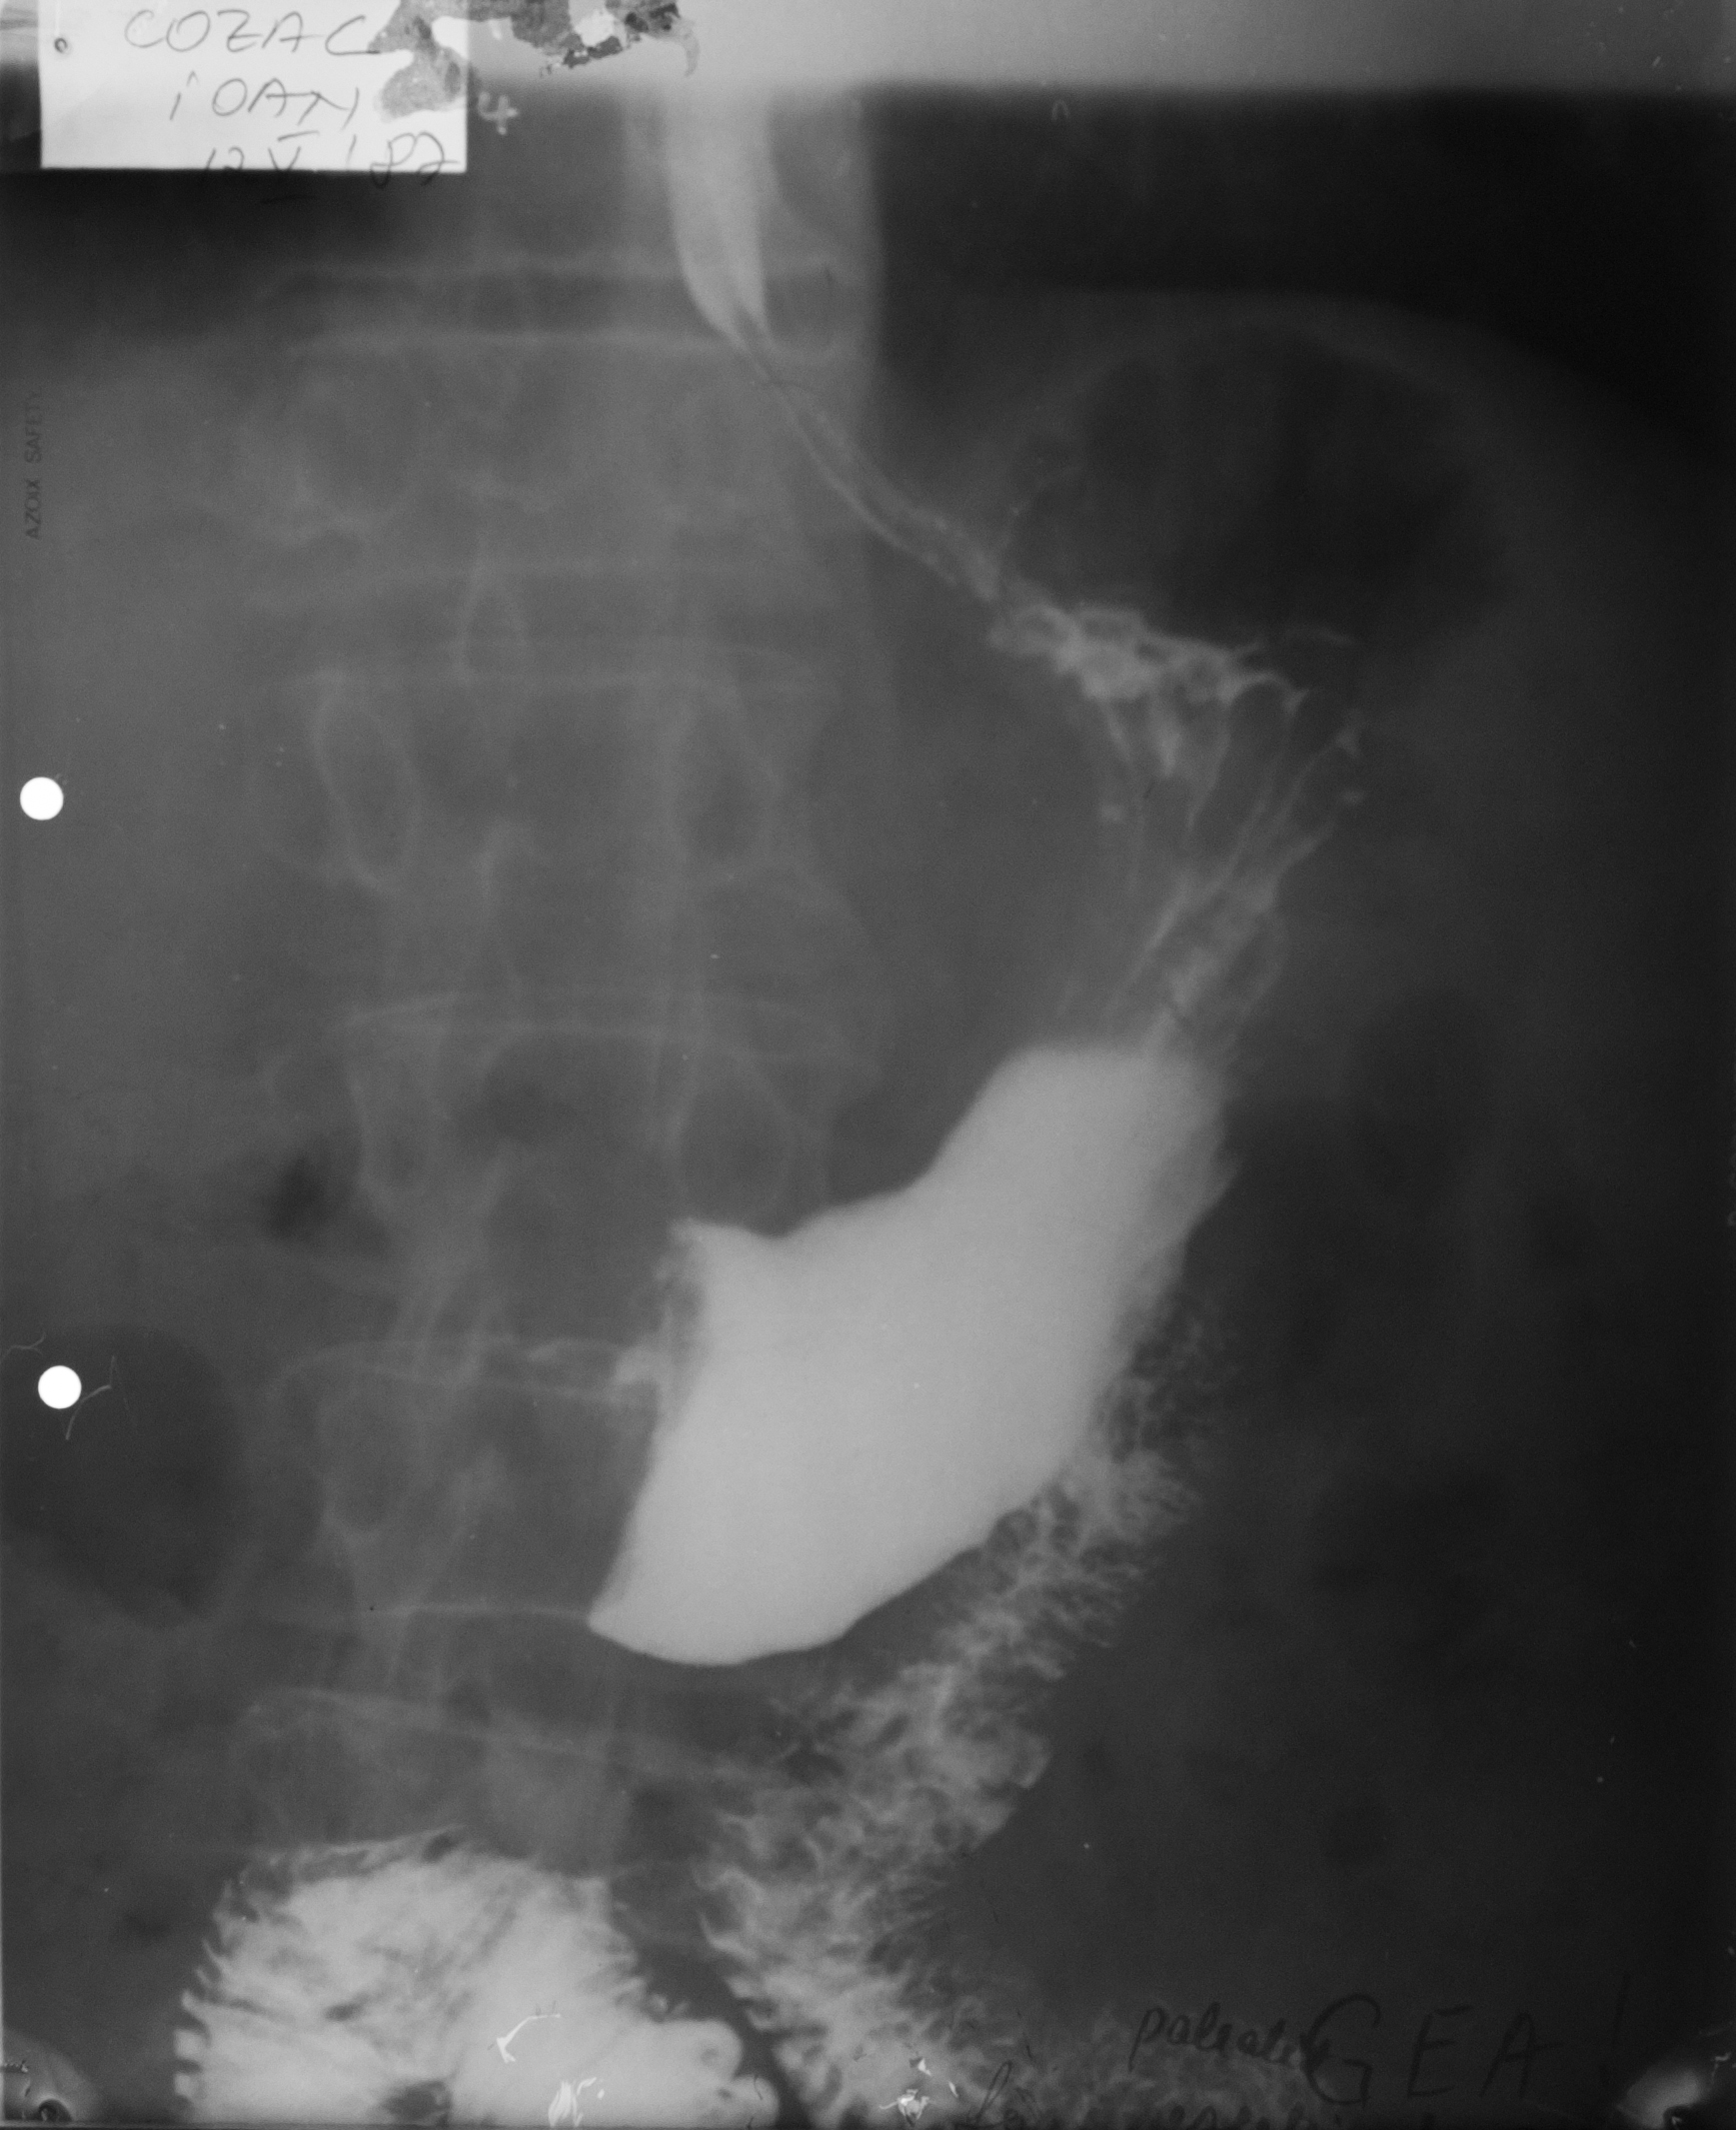

STOMAC NORMOTON(aspectul radiologic)

Tranzitul baritat al stomacului.Aspectul stomacului cu substanță de contrast:forma literei J cu fornix,corp,antru,canal piloric + bulb duodenal,D2(partea descendentă a duodenului

STOMAC ORIENTALIZAT/HIPERTON (aspect radiologic normal)

Stomacul hiperton este caracteristic persoanelor scurte și grase

STOMAC ALUNGIT (aspect radiologic normal)

Stomac alungit cu polul inferior aproape de nivelul crestei iliace.Este caracteristic persoanelor longiline

STOMAC DILATAT

Stomac destins cu substanță de contrast cu polul inferior aflat în micul bazin

Stomac dilatat cu mult lichid de secreție și stază gastrică